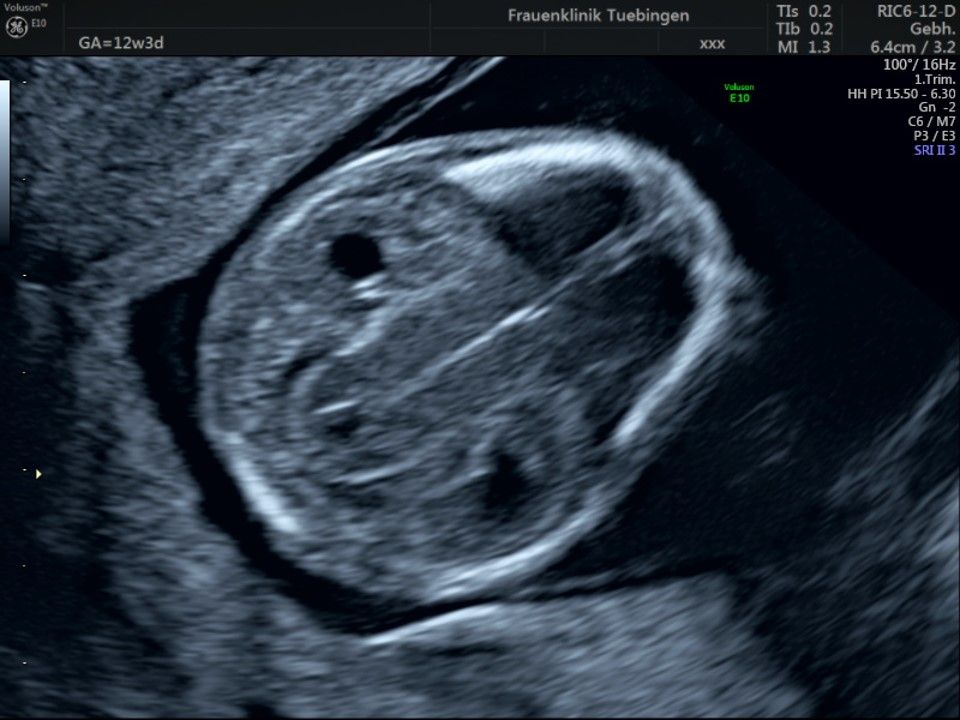

Im Rahmen des Ersttrimester-Screenings untersuchen wir die Organe des Feten mittels Ultraschall. Dabei machen wir auch gerne ein Bild für Sie.

Obwohl der Fet zu diesem Zeitpunkt erst zwischen 5 und 8cm groß ist, lassen sich bereits etwa die Hälfte aller schwerwiegenden Fehlbildungen erkennen bzw. ausschließen. Sollten wir eine Auffälligkeit sehen, werden wir mit Ihnen den Befund und das weitere Vorgehen ausführlich besprechen.

Die eigentliche Organuntersuchung findet um die 20.SSW (zweites Screening) statt. Das Ersttrimester-Screening und das zweite Screening sind sich ergänzende Untersuchungen und ersetzen sich gegenseitig nicht.